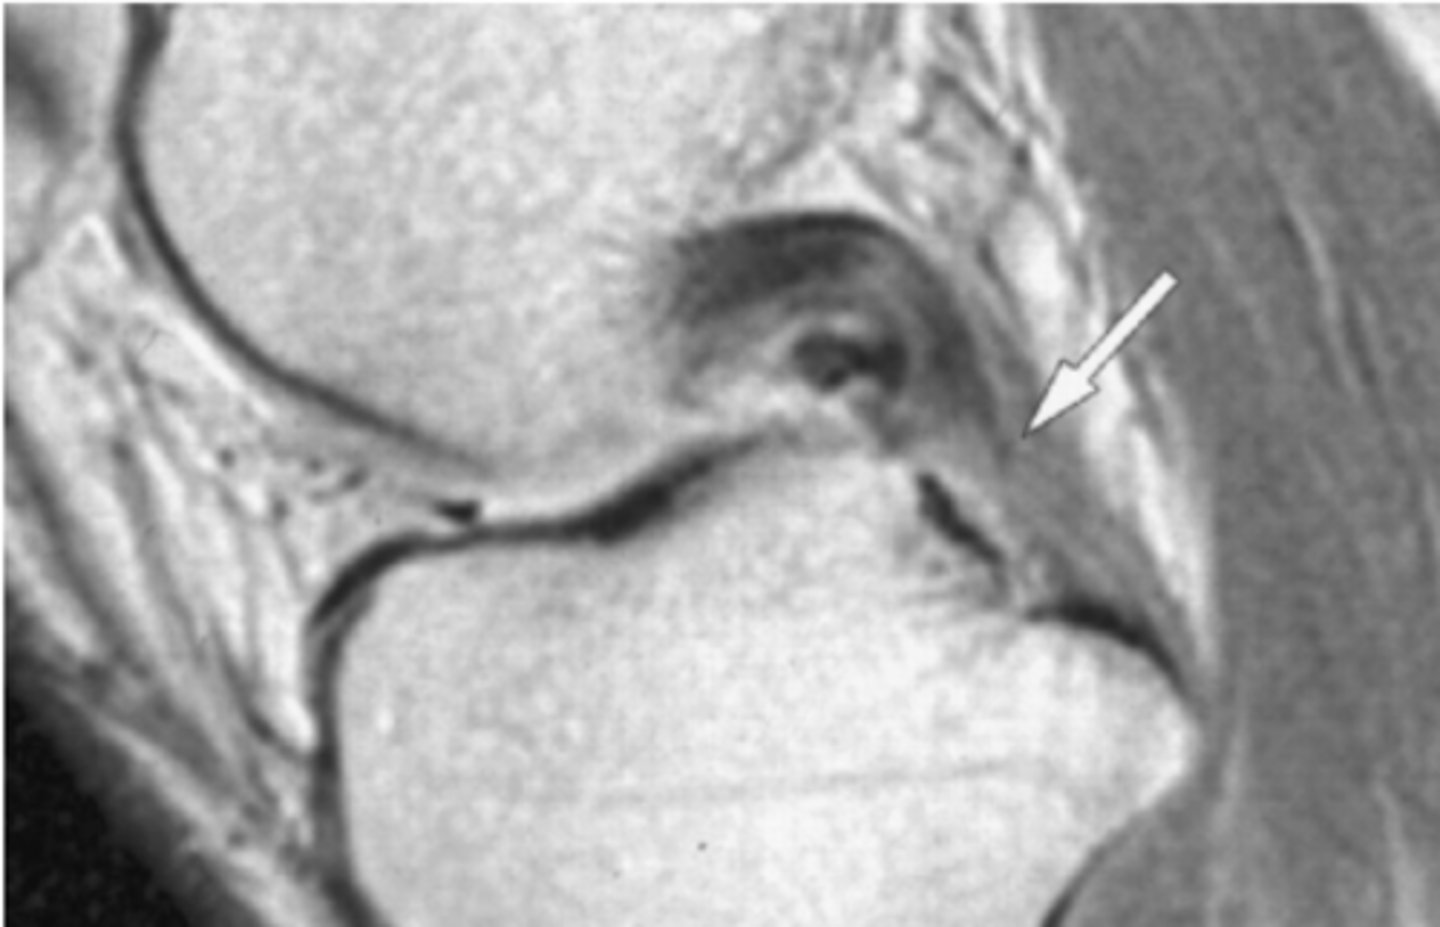

Tear of the PCL -- when ligaments curve like this and/or get wavey, it is a dead give-a-way that a tear is present

Define the pathology.